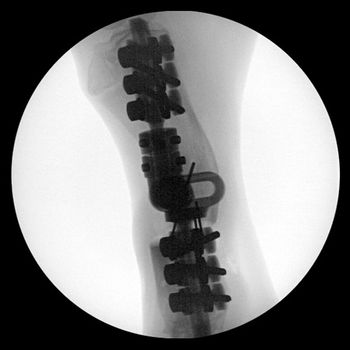

Fort Collins, Colo. - To save a dog's leg, a veterinary orthopedic surgeon tried something radical.